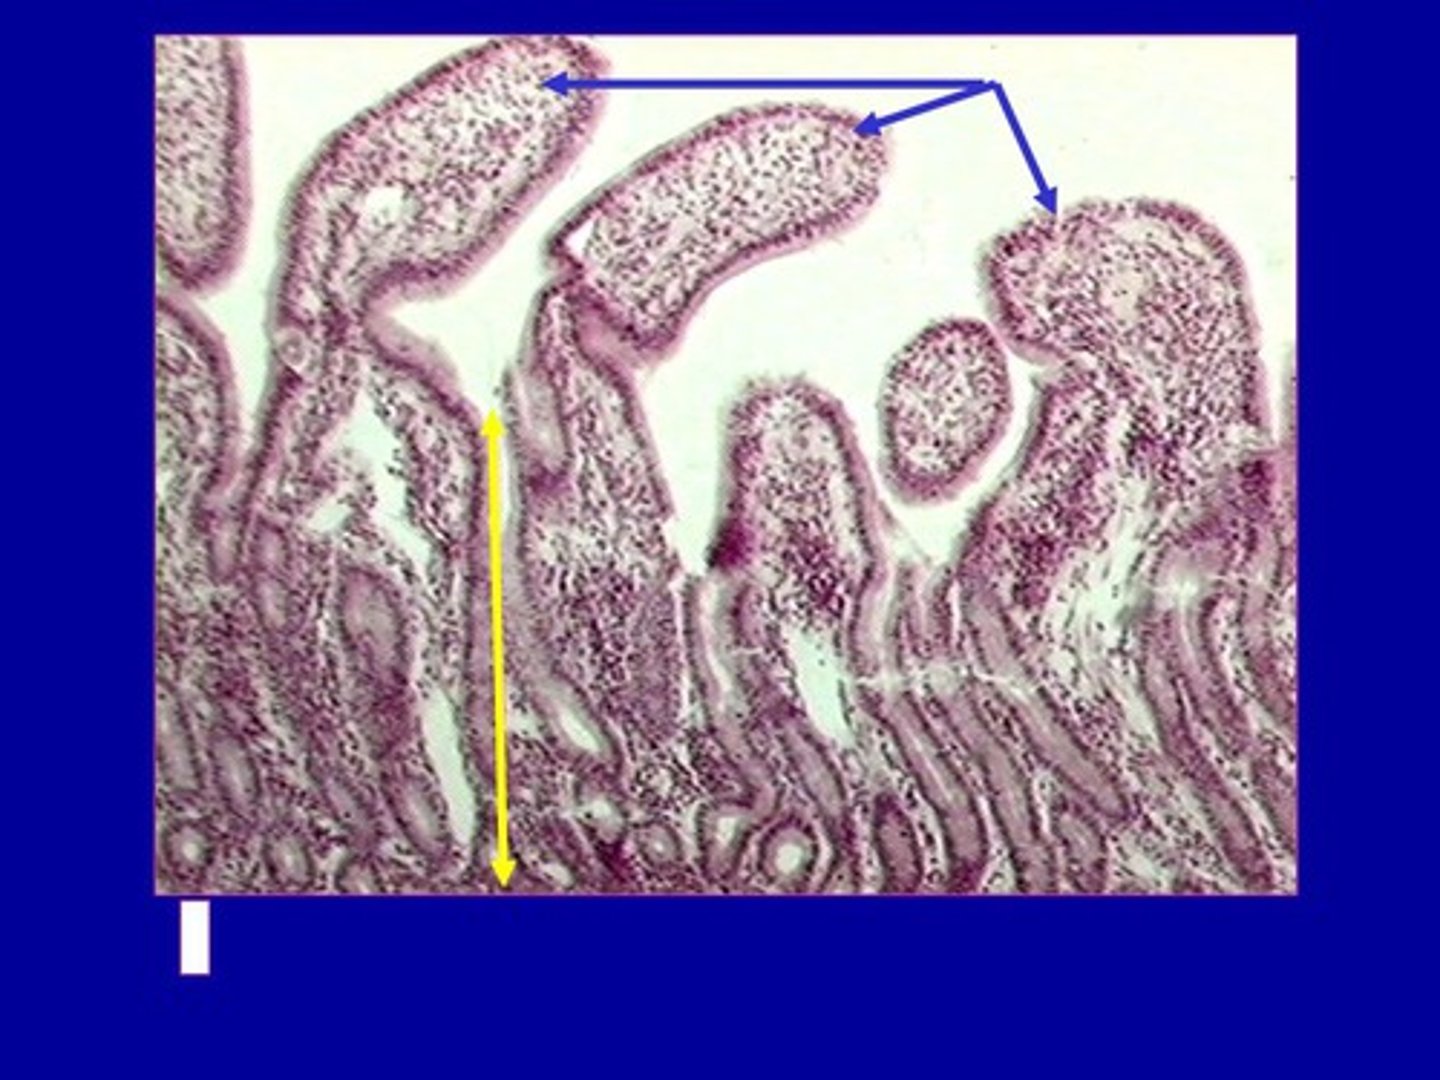

plicae circulares / circular folds

what are the folds

intestinal crypt

enterocyte

goblet cell